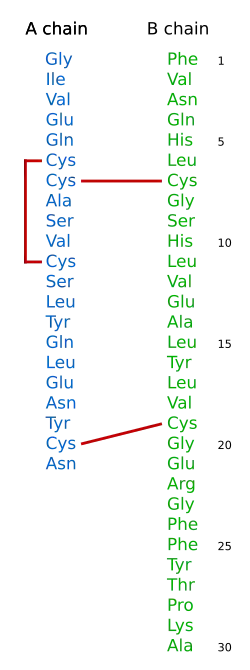

| Préproinsuline | ||

Formation de l'insuline à partir de la proinsuline. La préproinsuline est le produit de l'expression du gène INS et compte 110 résidus d'acides aminés. L'élimination des 24 résidus C-terminaux formant le peptide signal au niveau du réticulum endoplasmique donne la proinsuline, laquelle est convertie en insuline par élimination de 35 résidus entre les chaînes A et B, elles-mêmes réticulées par ponts disulfures. | ||

L'insuline est une hormone constituée de 2 chaînes polypeptidiques reliées entre elles par 2 ponts disulfures et 1 pont disulfure intrachaîne dans la chaine A : une chaîne A de 21 acides aminés, et une chaîne B de 30 acides aminés. La structure de l'insuline a été déterminée par Frederick Sanger. Ce fut l'objet du premier de ses deux prix Nobel, en 1958. La structure de molécules de plus en plus complexes peut être analysée, jusqu'à ce que, grâce à ses travaux sur la détermination par les techniques des rayons X Dorothy Crowfoot Hodgkin résolve enfin la structure de l'insuline, ce qui lui vaudra le prix Nobel de Chimie en 1969. L'insuline est produite par les cellules β des îlots de Langerhans du pancréas sous la forme d'une pré-pro-insuline constituée d'une seule chaîne peptidique, dont deux fragments, le peptide signal (23AA N-ter) est éliminé par l'action d'une enzyme, la signal peptidase qui va cliver le peptide signal entraînant la création des trois ponts disulfures, on obtient la pro-insuline qui subira l'élimination du peptide C par une autre enzyme, la PC1, ce qui va libérer un fragment central, tandis que les deux chaînes néoformées vont rester associées grâce aux ponts disulfures : enfin l'extrémité C-Terminale d'une des chaines va être clivée par l'action d'une carboxypeptidase E (CPE) pour devenir l'insuline sous sa forme mature, et donc active. La proinsuline a une structure très voisine de celle des deux principaux facteurs de croissance, IGF-1 et IGF-2, et des concentrations élevées de ces hormones permettent des effets biologiques par signalisation après liaison aux récepteurs des autres : hypoglycémie lors de sécrétion massive d'IGF-1 et d'IGF-2 par des tumeurs. L'insuline circule à des concentrations de l'ordre de la nanomole par litre.